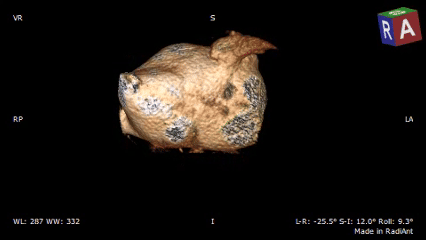

术前CTA确认心耳形态及位置

低位双分叶型左心耳

术前检查:心脏CT三维重建确认开口直径与心耳深度

RAO30度

CAU20度

左心耳大小20.1*17mm

RAO0度

CRA20度

左心耳大小20.3*15.5mm

RAO170度

CAU30度

左心耳大小20.2*17mm

CT三维平面左心耳开口形态及大小

左心耳开口近圆形,MPR周长66.4mm,化圆直径21.1mm,预选LAFDQ-23封堵器进行封堵